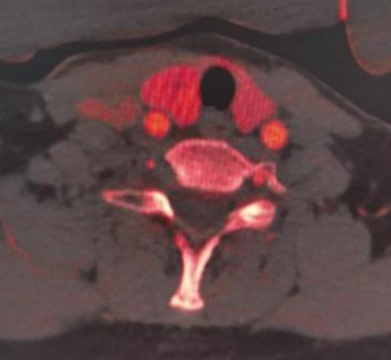

(a) (b) (c) (d)

(e) (f) (g) (h)

Figure 1. Examples of dual-energy CT arterial phase images, iodine uptake images, Rho/Z images, and pathological findings in three groups of patients with thyroid nodules (HE, ×100, H) (Rho/Z, Electron Density/Effective Atomic Number)

1. 三组甲状腺结节患者双能量CT动脉期图、碘图、Rho/Z图及病理图示例(HE, ×100, H) (Rho/Z,电子密度云/有效原子序数)